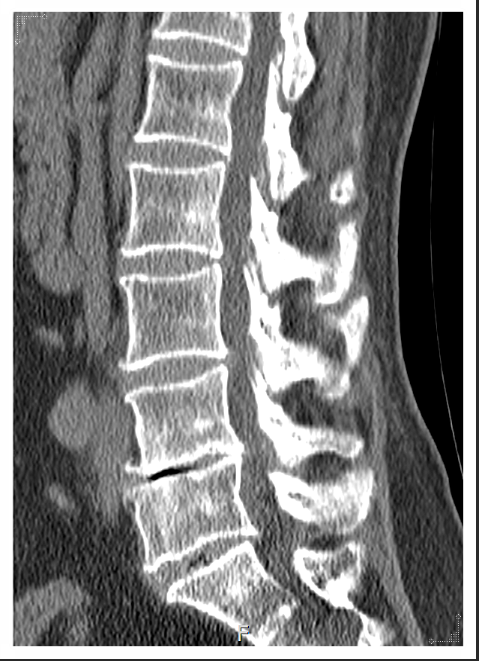

특히 요추 3번, 4번, 5번처럼 허리 아래쪽에 압박이 집중되면 디스크 증상과 신경 자극이 반복될 가능성이 커집니다.

디스크 파열이나 신경 압박은 허리 통증의 직접적인 원인처럼 보이지만, 사실상 결과에 더 가깝습니다.

우리가 놓치기 쉬운 진짜 원인은 틀어진 골반, 굽은 등처럼 누적된 자세 불균형입니다.

골반은 몸 전체를 지탱하는 중심 받침대 역할을 합니다.

이 받침대가 기울어지면 허리 근육과 디스크가 그 부담을 대신 떠안게 되는데요.

허리통증 한의원 등에서 골반과 척추를 함께 교정하면 요추에 집중되던 체중 압력을 자연스럽게 분산시킬 수 있습니다.